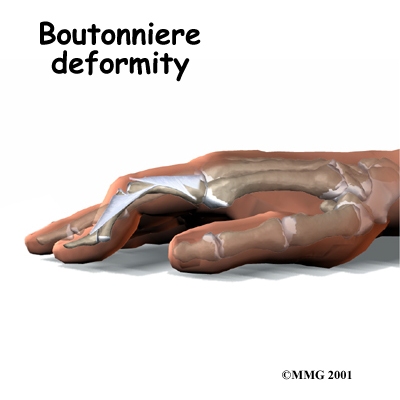

Both rheumatoid arthritis and osteoarthritis can affect the IP joints of the fingers. The IP joints may begin to flex (bend) or hyperextend (over straighten), causing characteristic finger deformities. occurs when the middle finger joint (the PIP joint) becomes loose and hyperextended, while the DIP joint becomes flexed. When the PIP joint flexes and the DIP joint extends, a forms.

Related Document: Combined Therapy Specialties Guide to Boutonniere Deformity of the Finger